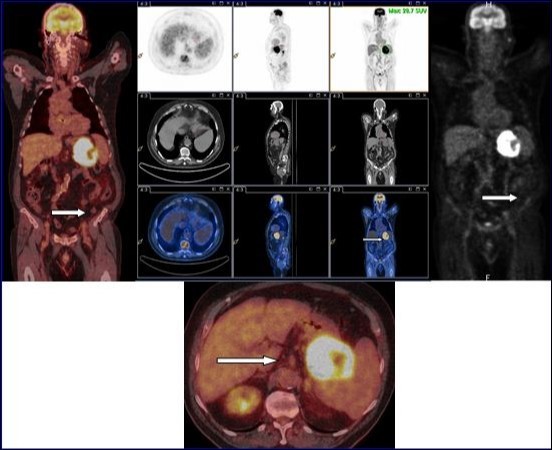

18F-FDG PET-CT with injection of intravenous iodinated contrast demonstrated an intense and diffuse hyper metabolism at the primary tumor of the stomach. No morphological or metabolic argument features of secondary manifestation of this tumor were observed in the whole-body (Figure 2). Partial gastrectomy with resection of the proximal 2/3 of the stomach, the spleen, the body and tail of pancreas and the left transverse colon was performed.

Figure 2.18F-FDG PET-CT with injection of intravenous iodinated contrast demonstrated an intense and diffuse hyper metabolism at the primary tumor of the stomach. No morphological or metabolic argument features of secondary manifestation of this tumor were observed in the whole-body.